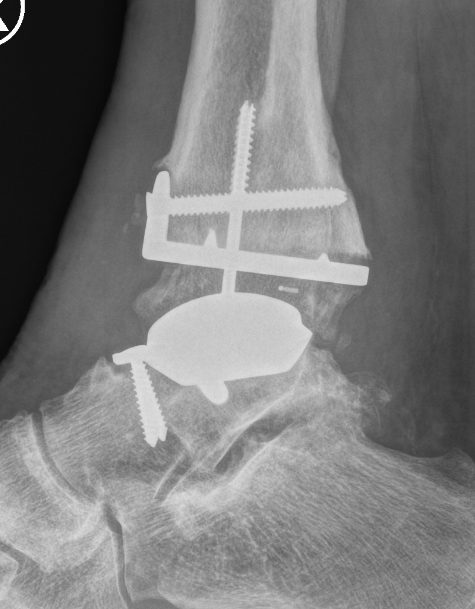

CT

Evaluate bone stock to determine if TAR is appropriate

Tibial cut

- distal alignment jig / extramedullar jig +/- image intensifier +/- patient specific jigs

- resect few mm above eroded bone

- preserve medial and lateral malleolus

Talar dome resurfacing

- jig to make chamfer cuts

Insert mobile / fixed bearing